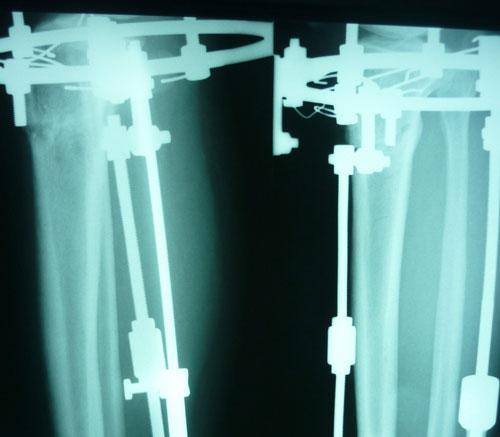

Также высылаю снимки, сделала рентген свежий срок 3 мес, вот такое получилось качество,левая боковая не очень видна((.

Посмотрите действит-но ли можно снимать,или еще походить, мне как неспециалисту непонятно((( Я смотрела снимок Бакты перед снятием- там тоже есть черные места,но тем не менее мозоль хорошая.

Здравствуйте,Bella! У Вас всё срослось - пере срослось. Давно пора снимать аппараты. Приезжайте.